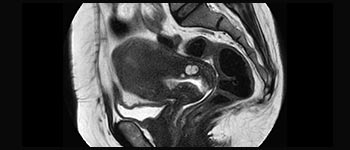

Becken

Weibliches Becken